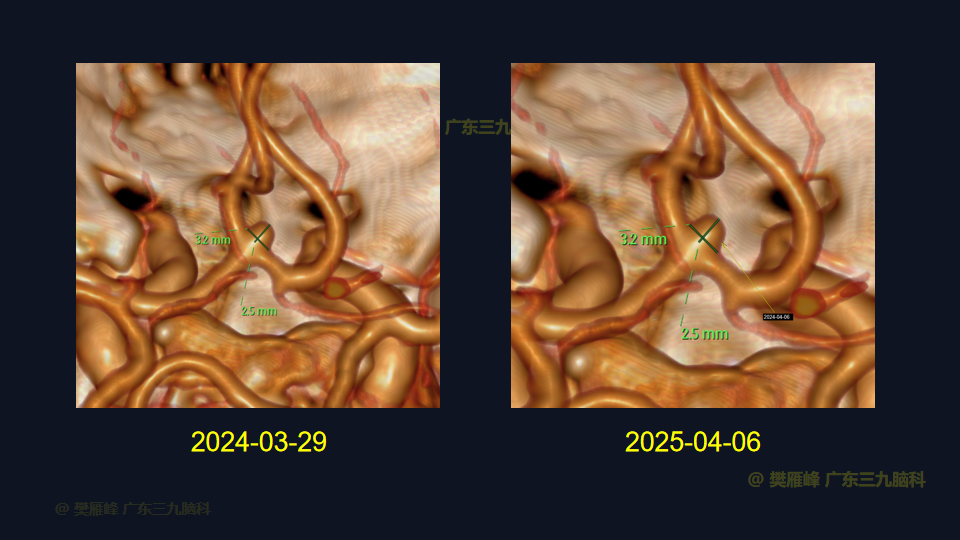

在这个二维手术视频中,展示了一种经翼点入路显微夹闭未破裂的前交通动脉瘤的方法。患者是一名61岁的男性,发现前交通动脉瘤1年较前增大,神经影像学显示前交通动脉大小约为3.6×3.3mm的囊状突起影。他接受了开颅手术夹闭动脉瘤的方法,术中血管造影显示动脉瘤完全夹闭。术后无新发神经功能。我们展示了细微的动脉分离技术和动脉瘤夹闭技术的细微差别和技术要点,以及手术技术。